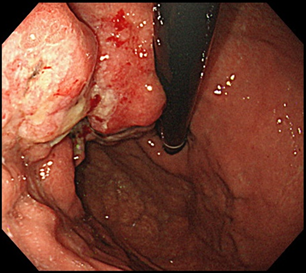

胃がんとは?

胃がんは、胃の壁の最も内側にある粘膜内の細胞が、何らかの原因でがん細胞になることから始まります。胃がんの患者数はゆっくり減少しています。胃がんの罹患率と死亡率は男性の方が女性より高く、年齢別にみると40歳未満では男女差は小さく、40歳以降にその差が開きます。

胃がんの発生要因としては、ほとんどの場合がヘリコバクター・ピロリ(ピロリ菌)の感染による慢性胃炎からの発がんです。喫煙や食塩・高塩分食品の摂取が、発生する危険性を高めることが報告されています。近年、ピロリ菌陰性の胃がんも少しずつ増えてきており、ピロリ菌が陰性だから胃がんにならないとは言えないのです。

早期胃がん

進行胃がん

胃がんの深さが粘膜および粘膜下層にとどまるものを「早期胃がん」、粘膜下層より深いものを「進行胃がん」といいます。

早期がんであればESDによる内視鏡的切除を検討し、内視鏡的に切除できないと判断される場合は、外科手術による切除が考慮されます。腹腔鏡を用いた手術が多くの場合行われますが、腫瘍が大きい場合や腹部手術の既往がある場合は開腹切除術となります。一部の大学病院などの先進施設では、ロボット手術(ダヴィンチ)も保険適応になり積極的に行われています。